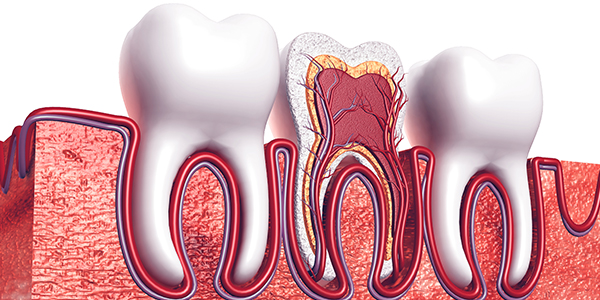

歯の神経や血管が入っている細い管を「根管」といいます。その中からむし歯に汚染された神経や血管、歯質を除去して細菌を残さないように洗浄・消毒してから、薬剤をすき間なく注入して密閉する処置を「根管治療」といいます。治療した箇所には土台を作り、被せ物を装着して歯の機能を補います。